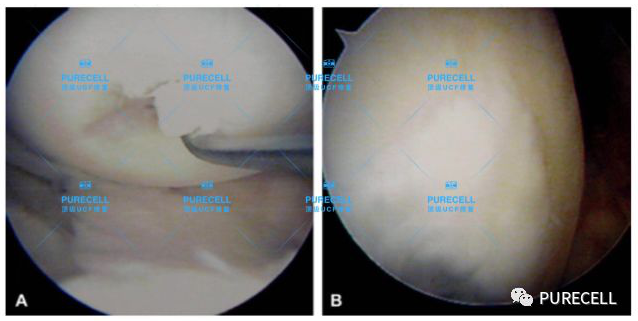

PURECELL首席科學家以及運動醫療專家已經驗證了UCF對膝關節修復的有效性,上圖是UCF軟骨及半月板修復前後影像對比